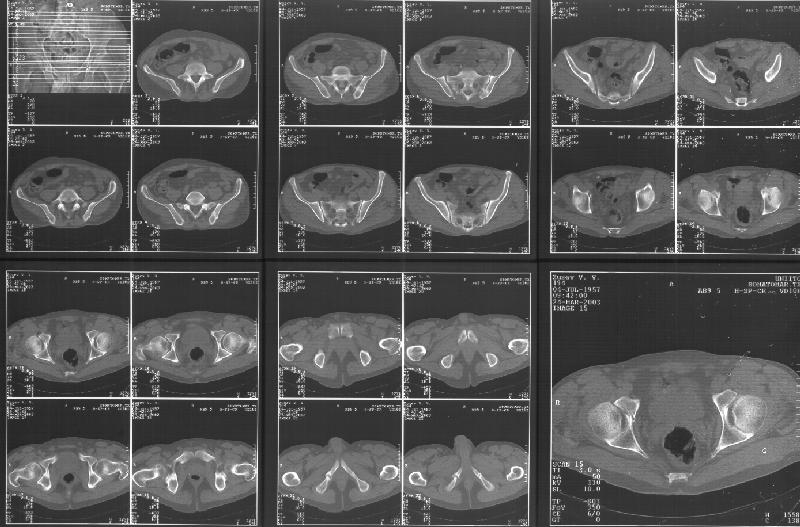

Прилагаю свежую КТ таза.

Картинки см. ниже, левая - с экранным разрешением, вторая - полноразмерная, ~900 кб.

КТ в экранном разрешении

Полноразмрная картинка, около 900 кб

Based on the CT images you provided, he appears to have a nonunion of the the right ischium, which would explain his symptoms. General principles of treatment of hypertrophic (which this appears to be) nonunions suggest rigid fixation, but I'm not sure what the best approach would be. Could get a lag screw across the fracture through a Kocher-Langenbeck approach or plate osteosynthesis through direct ischial approach, but perhaps Chip, Adam or someone with more pelvic fracture experience could enlighten us all.

I think this is just a pelvic ring disruption that has gone on to a non-union. The arrow is pointing to the inferior ramus non-union, and

the sup ramus is a high "root" fracture, right near the pecten. The sup ramus fracture enters the tab - you could call it an acetabular

fracture - but down here in Dallas we treat these acutely as stable pelvic ring injuries. The fracture in the anterior portion of the

acetabulum is so low it doesn't seem to cause much trouble.

His R sacroiliac joint is opened anteriorly a little bit - the "unreduced posterior lesion" Alex mentioned in his first post. My earlier post about plating, bone grafting, etc., is all wrong.

What you have is a pelvic fracture that hasn't healed after 4 months or so, with a minimal deformity.

I think what I would offer the guy is a percutaneous iliosacral screw to stabilize and improve the SI joint alignment, coupled with a perc anterior column screw to stabilize the high ramus fx. These screws aren't easy to place, and have a host of potential problems and complications. But, I think they would work.

Как Вы сами видели на томограммах, грубых деструктивных явлений крестцово-подвздошного сочленения не определяется( маркировка правая -левая сторона не видна), определяется сравнительно незначительное расширение суставной щели с одной стороны и не более того.

Виноват, первый раз не обратил внимания на возможность полноформатного просмотра томограмм. В этой связи -дополнения к своему первому комментарию: сросшийся перелом вертлужной впадины справа, L5-S1 спондилоартроз, расширение суставной щели крестцово-подвдзошного сочленения справа может компрометировать его стабильность и вызывать локальные боли, но вряд ли это может давать двусторонние проявления в нижних конечностях. Все-таки миелограмма или ЯМР желательно иметь, чтобы определиться в тактике.